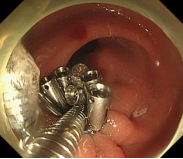

胃内粘膜下隆起,术前超声提示来源于固有肌层,术前判断需胃壁全层切除。

术中所见与术前判断相符,行内镜全层切除术EFTR,术后严密封闭创面,患者2日后安全出院,术后病理诊断胃间质瘤。